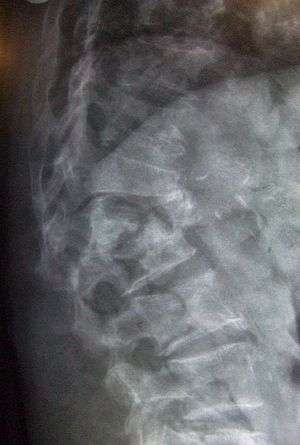

| Lateral spine X-ray showing osteoporotic wedge fractures of L1/2. | |

A spinal fracture, also called a vertebral fracture or a broken back, is a fracture affecting the vertebrae of the spinal column. Types of spinal fracture include vertebral compression fracture and burst fracture, cervical fracture, Jefferson fracture, Hangman's fracture, Flexion teardrop fracture, Clay-shoveler fracture, Chance fracture and Holdsworth fracture.

Vertebral fractures of the thoracic vertebrae and lumbar vertebrae are usually associated with major trauma and can cause spinal cord damage that results in neurological deficit.